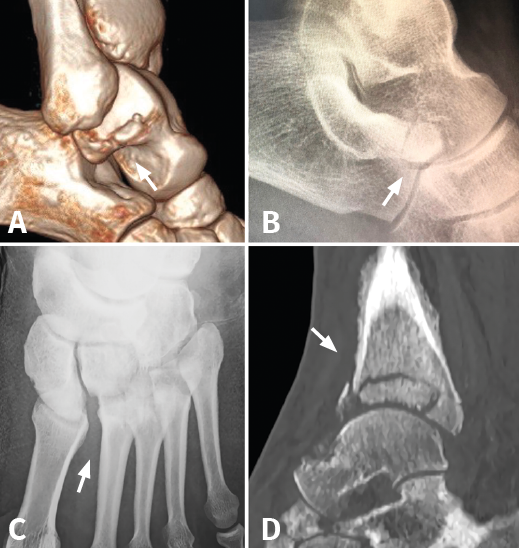

Figura 2. A: fractura pars lateral del astrágalo (snowboarder’s fracture); B: fractura pars anterior del calcáneo; C: lesión sutil de Lisfranc; D: neuroartropatía diabética de Charcot de la tibia distal.

El tiempo medio de demora hasta el diagnóstico fue de 38,5 días (rango: 2-270 días). En 14 casos (56%) el diagnóstico definitivo se realizó en urgencias tras requerir el paciente una nueva valoración, al considerar que la evolución no estaba siendo la adecuada. La prueba complementaria que permitió la detección de la lesión fue en 6 casos (24%) la misma radiografía realizada previamente, en la cual se podía visualizar la lesión; una nueva radiografía diferente a la inicial en 6 casos (24%); la TC en 10 casos (40%); y una RM en 3 casos (12%) (Figura 2).